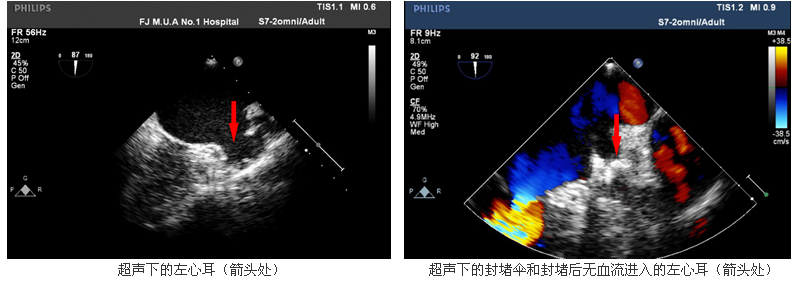

柴大军副教授介绍,房颤患者是临床最为常见的心律失常之一,病人一般表现为心悸、疲乏、气短等症状,患有房颤的患者,血液流通不畅,容易在左心耳淤滞,进而形成血栓。左心耳是从左心房伸出的耳状小囊,是左心房的主要组成部分。在非瓣膜性房颤中,90%以上血栓的形成与左心耳有关。房颤患者中风风险是普通人的5倍,而由房颤引起的中风通常更严重,致死、致残率更高,也更容易复发。目前治疗房颤引起的血栓栓塞性疾病的常规治疗方法是服用抗凝药,服药过程漫长而且作用局限,无论是华法令还是新型抗凝药,大约21-28%的患者会因药物不良反应出血等并发症而停药。

经皮左心耳封堵术是近年来发展起来的一种预防房颤患者血栓栓塞事件的创新治疗术式。它适应房颤合并有下列危险因素之一者,包括:高龄、高血压、冠心病、糖尿病、心衰、中风的患者,尤其是既往容易出血、有出血史的患者,更不适合终身药物抗凝治疗。该手术无切口,仅需在股静脉穿刺一个针眼,通过导管将一左心耳封堵器安置在左心耳开口部位,达到封闭左心耳,封预防左心耳内血栓脱落引起的血栓栓塞,从而避免缺血性脑卒中和全身性栓塞的发生。左心耳封堵术能消除患者对于长期抗凝治疗的依赖,避免了患者因抗凝药物所产生的不耐受、出血事件和依从性等问题,也为对抗凝药物具有禁忌证的患者带来了新希望。